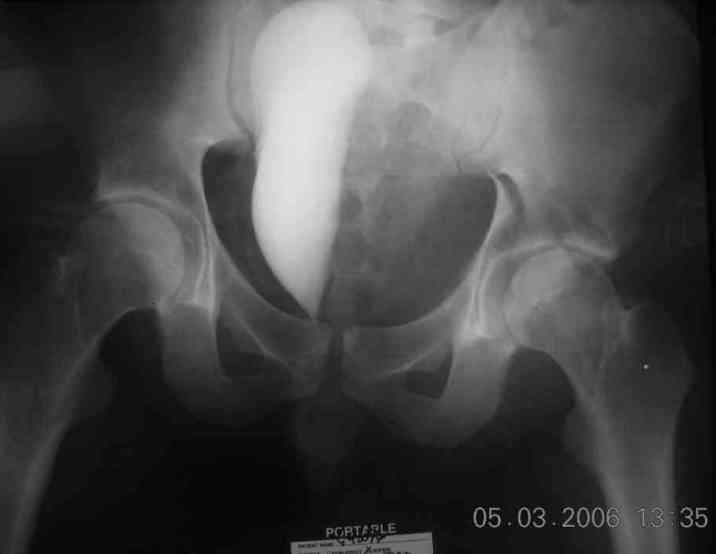

good morning,

the case that I found is a 20yo male, MCC. his AP pelvis shows an interesting position of his bladder. it is pushed aside by a hematoma from SGA injury. we did a limited lateral window approach for the anterior column first, pt bumped up/supine. then closed and repositioned for KL. I could not find intra-op photos of cases when we did only a small incision for the AC screw (but they do exist!!). the lateral window is available for reduction assessment if a KL approach is being used. in the lateral position this window is available. the prone position definitely takes pressure off of the post column and facilitates reduction. in the lateral position a schantz pin in the ischial tub +/- bone hook in sciatic notch helps with PC reduction. the lateral position also gives better airway access for anesthesia. airway problems are rare, but prone position seems to be a bit more of a challenge to exchange the tube, or reintubate altogether. just something further to debate!